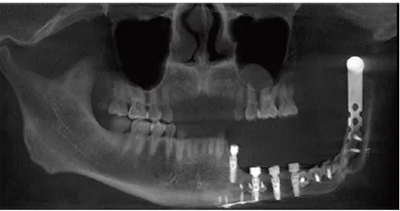

種植體植入后拍攝錐形束CT(cone-beam computed tomography,CBCT)顯示種植體在位,復(fù)合基臺對接在位,骨愈合良好(圖6)。